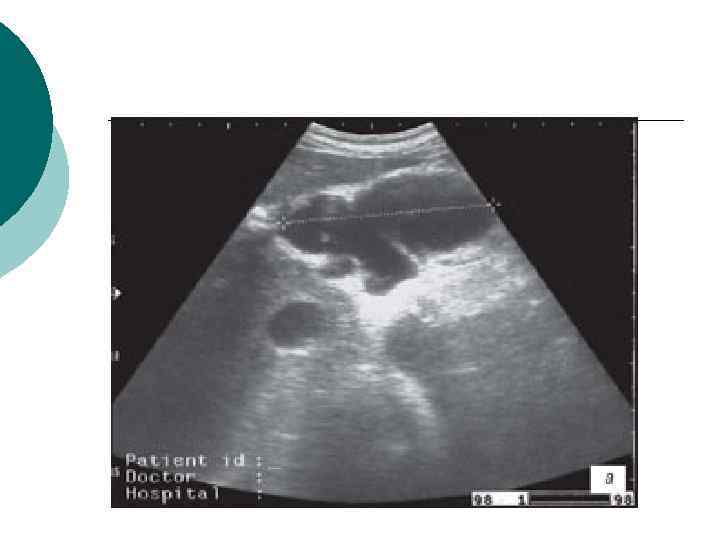

¡ ¡ Ультразвуковое сканирование брюшной полости На основании данных ультразвукового исследования вычисляется объем образования, оценивалют изменения поджелудочной железы, определяют наличие секвестров. Чувствительность УЗИ в диагностике составляет 99%, специфичность – 55, 5%. К достоинствам этого метода исследования следует также отнести его доступность, неинвазивность и отсутствие противопоказаний. Однако относительно низкая специфичность приводит к значительным трудностям в дифференциальной диагностике острых жидкостных скоплений, острых кистойдов и острых абсцессов поджелудочной железы (согласно позициям Атлантской классификации острого панкреатита, 1992 г).

Инфильтрат в проекции большого сальника с анэхогенным включением до 4 см (абсцедирование).